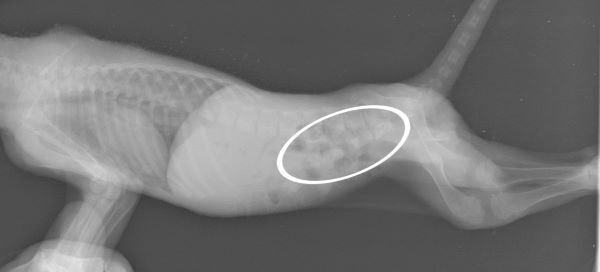

非常に衰弱している様子でしたが、幸い外傷はなく、レントゲンでは骨折もありませんでした。

この時、お腹の中にはかなりの量の便が溜まっていることが確認できました。

爪もしっかりとしていて歯もかなり生えていることから生後2週間ほどだと考えられますが、かなり痩せているようです。